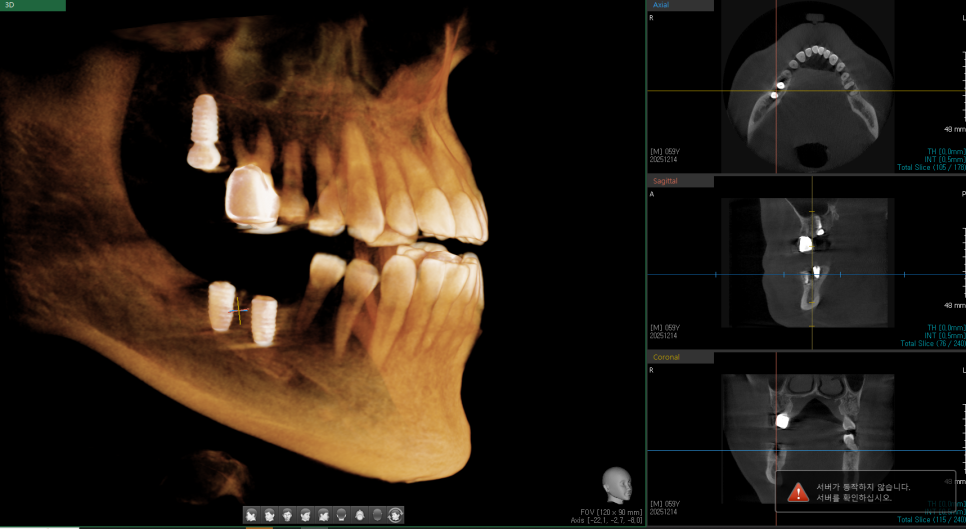

다행히 골질이 좋아서, 발치 후 즉시 임플란트 식립을 진행했습니다.

식립 이후 임플란트가 잘 유지되어서, 이후 보철물 잘 올리고 마무리했습니다. 환자분이 지금까지 너무 잘 쓰고 계시다고 하네요 :)